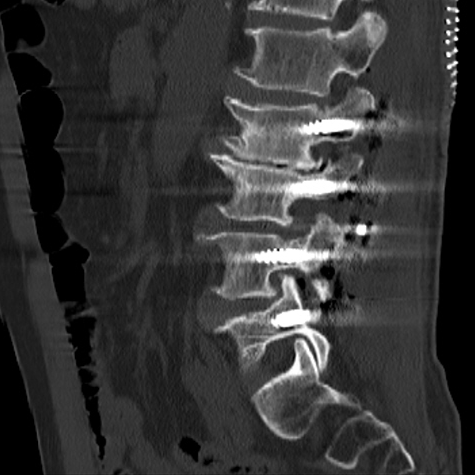

术后复查X线、CT

椎弓根螺钉内固定技术是目前脊柱手术中最常应用的固定技术,但在椎弓根置钉过程中存在损伤神经与血管的风险。提高置钉安全性及成功率一直是脊柱外科医师研究的重要内容。

陈勇主任团队顺利为患者置入椎弓根螺钉。术后患者腰腿痛症状较术前明显缓解,肢体活动无障碍,术后3天即在脊柱支具外固定的辅助下下地行走,术后第7天患者恢复情况良好,顺利出院。